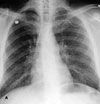

Fever and abdominal pain in man with prior stab wounds: The PA radiograph (A) reveals diffuse miliary lung nodules. There is no evidence of lymphadenopathy or pleural effusion. A chest film obtained 7 days earlier was clear.

CT findings. A CT scan of the chest is obtained 2 days later for further characterization of the nodules (B). The scan demonstrates extensive miliary nodules randomly distributed throughout both lungs. The nodules are superimposed on diffuse ground-glass opacities (hazy areas of opacity that do not obscure pulmonary vessels). Septal lines are also present at the lung bases. Compared with the images of the lung bases seen on the abdominal CT scan, the nodules have rapidly progressed over 2 days.

Like chest radiographs, CT scans of patients with pulmonary talc granulomatosis usually reveal a diffuse pattern of micronodules. As in the case presented here, the CT scan may show additional findings, such as ground-glass opacity and septal lines. Additional CT findings may include conglomerate masses (with the occasional presence of high-attenuation foci) and lower lobe-predominant panacinar emphysema.2 Several investigators have reported a progression of talc disease on serial imaging studies similar to the progression found in silicosis, with a diffuse fine nodular pattern progressing to upper lobe, high-attenuation conglomerate masses.2-5